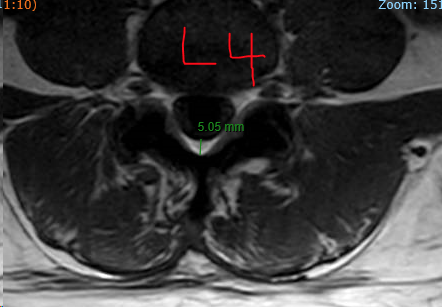

Regarding epidural space at different levels. I have noticed over the years that there doesn't seem to be much space (but i'm sure there is plenty of potential space) at L5 - at least while the person is lying supine in an MRI scanner.

Here are two random l-spine MRIs on the scanner from today, T1 IMAGES to highlight the fat so epidural space is well visualized. This pattern is very reproducible.

PATIENT #1

Very interesting observations and images of L5-S1. Thanks for posting.

I do find myself often at L5-S1 for ILESI as it lures you in with that wide open interlaminar window. I often can’t see any interlaminar space at L4-5 because of all of the pathology commonly there. However; perhaps because of the smaller epidural space and thin LF, I see a lot of mixed epidural and intradural spread of contrast.